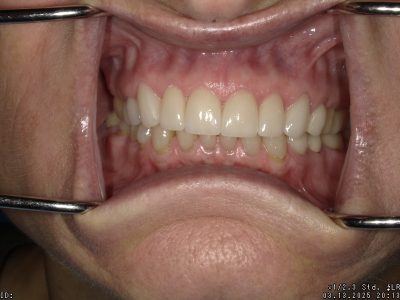

A case done with a combination of Crowns and Veneers on her upper anterior teeth.